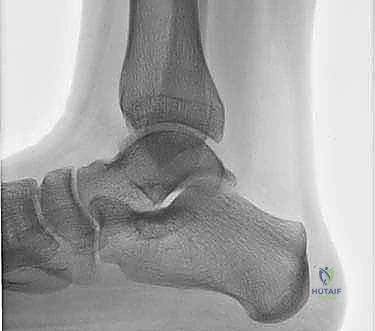

- الأشعة السينية (X-rays): تُستخدم كخطوة أولى لاستبعاد الكسور العظمية الكبيرة والتهاب المفاصل المتقدم. في بعض الأحيان، يمكن رؤية "ظل" أو كيس عظمي يشير إلى وجود آفة.

- التصوير بالرنين المغناطيسي (MRI): هو المعيار الذهبي (Gold Standard) لتشخيص OLTs. يُظهر الرنين المغناطيسي الغضروف بدقة عالية، ويحدد حجم الآفة، عمقها، وحالة العظم تحت الغضروفي (مثل وجود وذمة عظمية - Bone Marrow Edema).

- الأشعة المقطعية (CT Scan): يطلبها الدكتور هطيف أحياناً للحصول على خريطة ثلاثية الأبعاد دقيقة للعظم، مما يساعد في التخطيط الجراحي وتحديد حجم الرقعة العظمية المطلوبة للزرع.